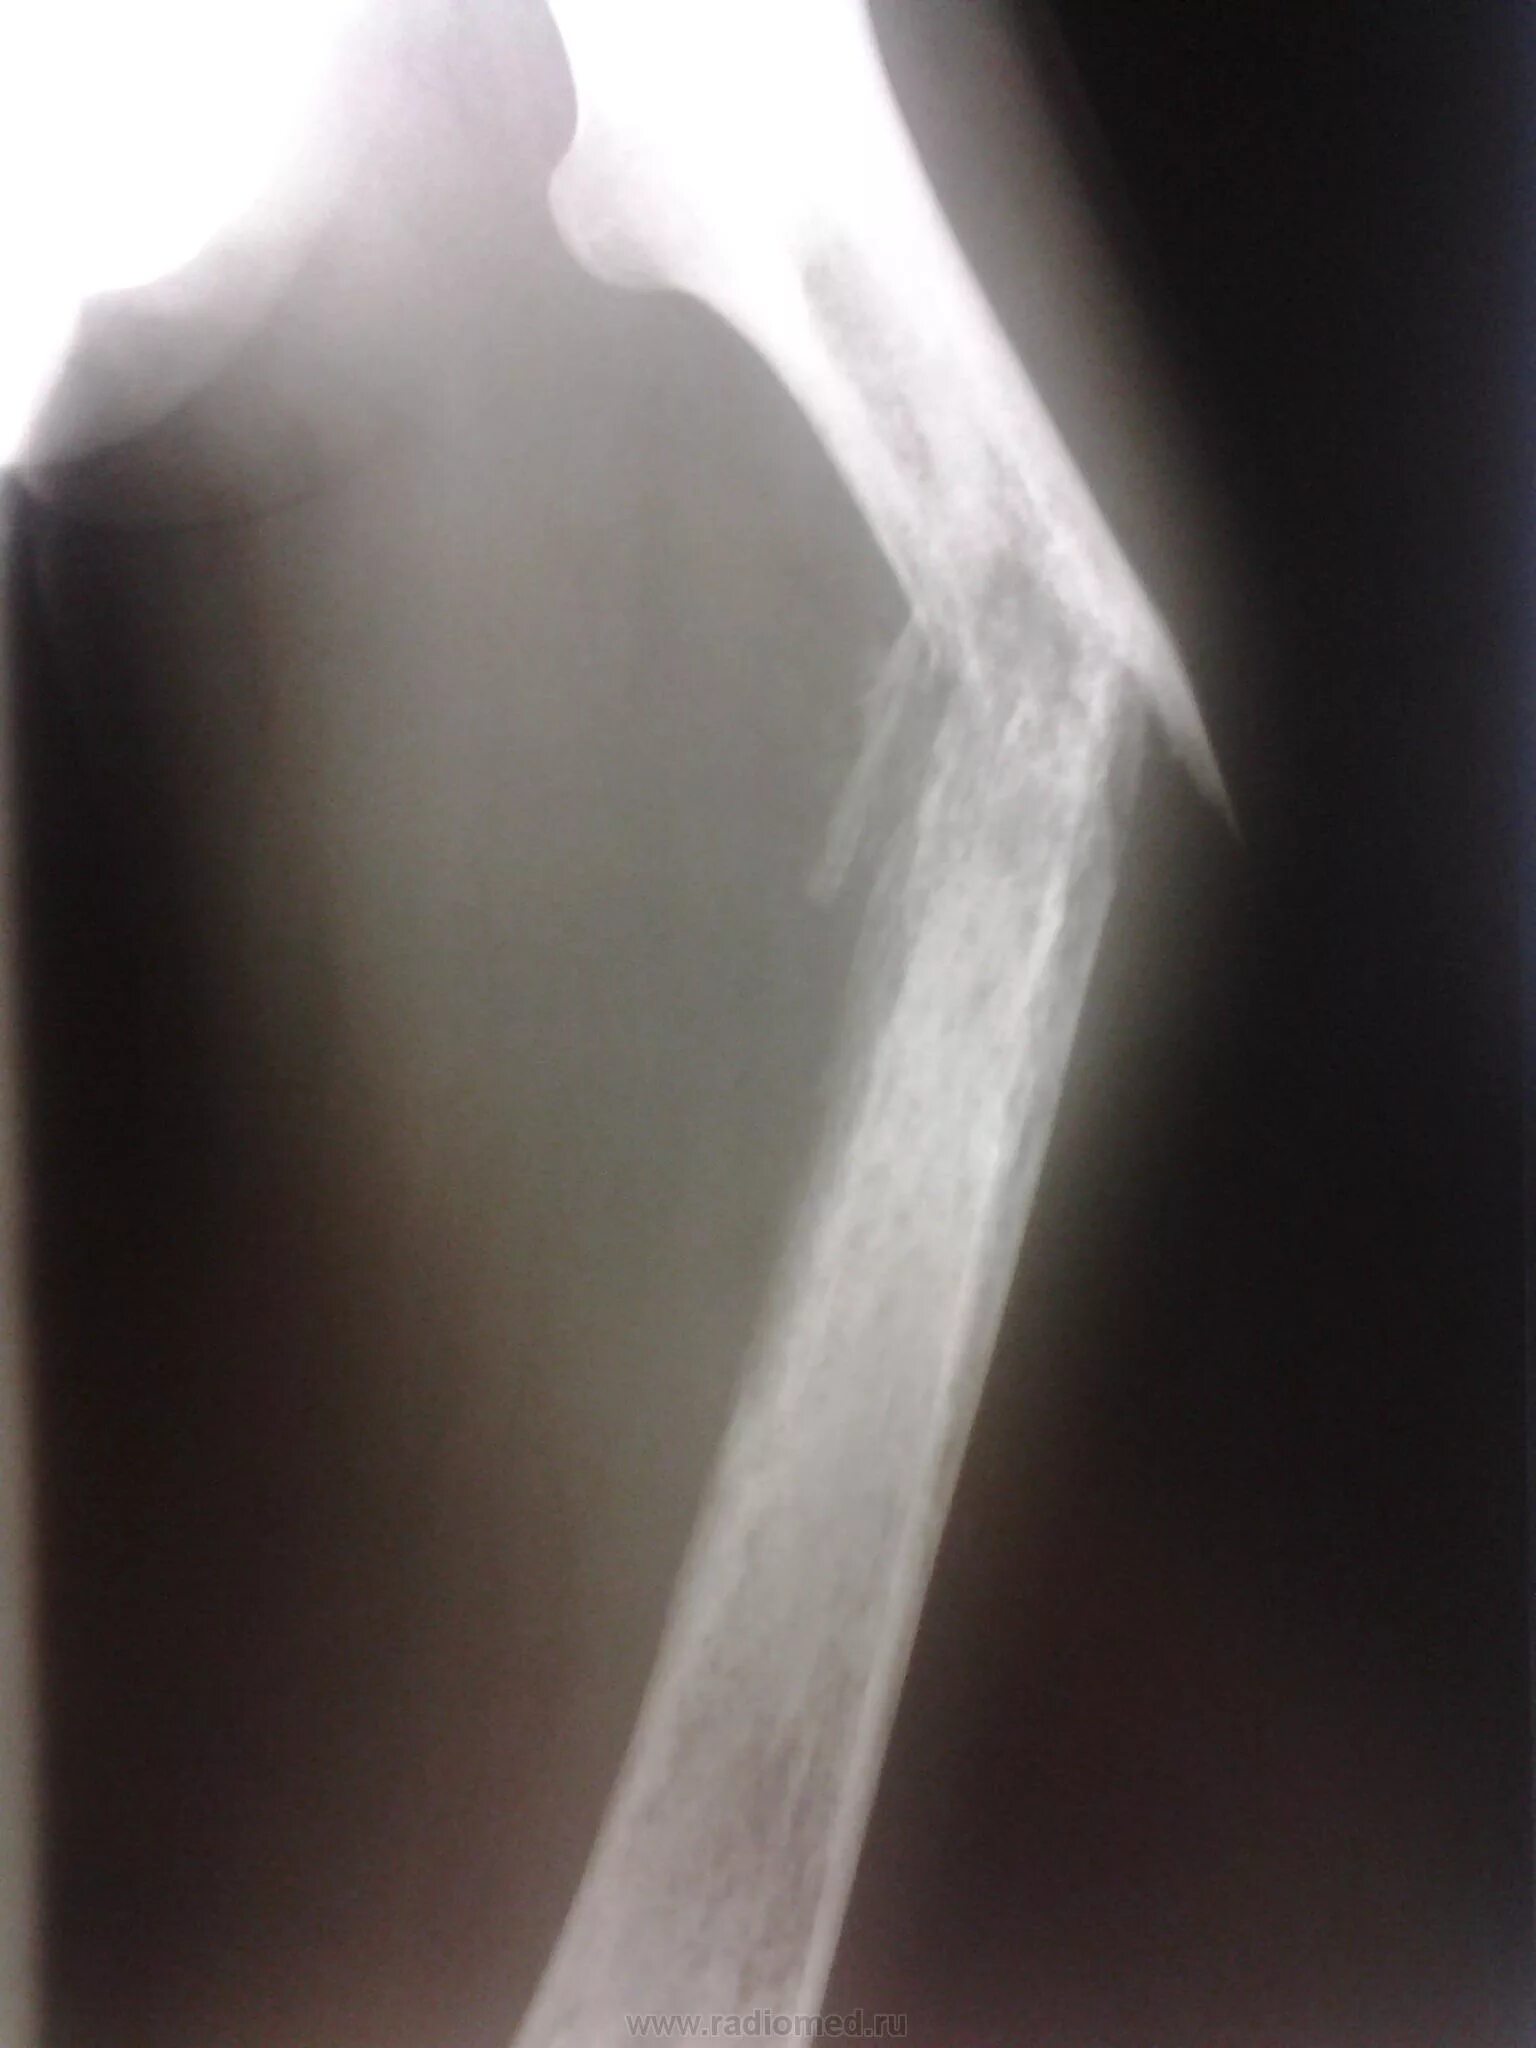

Патологический перелом бедра